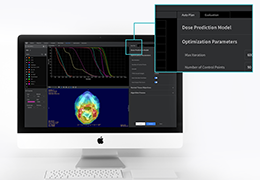

ART-Plan™ Artificial Intelligence Contouring